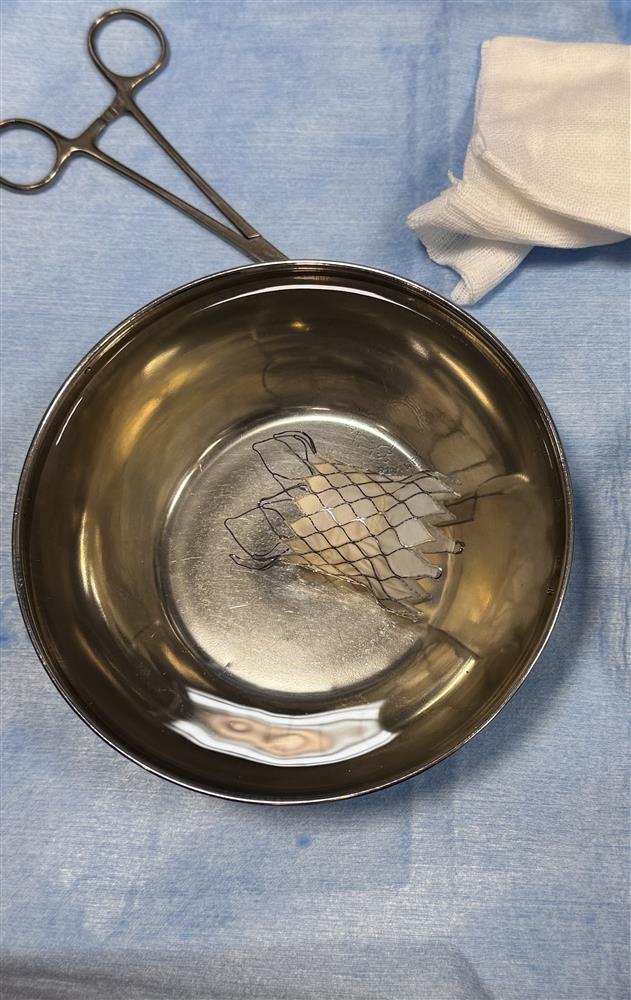

این پروسیجر پیشرفته در سرویس فوق تخصصی قلب و عروق بیمارستان فوق تخصصی مدائن زیر نظر مستقیم دکتر علی اکبر زینالو فوق تخصص قلب کودکان برای بیمار با سابقه مادرزادی تترالوژی فالوت قلب جهت جاگذاری دریچه مصنوعی فلزی از طریق اینترونشن با نتیجه بسیار خوب انجام شد.

این اقدام که در سطح کشور بسیار کم انجام میشود گامی مهم در ارتقاء خدمات درمانی بیماران قلب و عروق به شمار می رود.